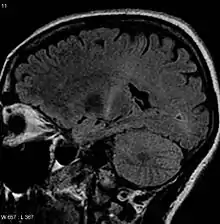

The defining feature of ALS is the death of both upper motor neurons (located in the motor cortex of the brain) and lower motor neurons (located in the brainstem and spinal cord).[89] In ALS with frontotemporal dementia, neurons throughout the frontal and temporal lobes of the brain die as well.[57] The pathological hallmark of ALS is the presence of inclusion bodies (abnormal aggregations of protein) known as Bunina bodies in the cytoplasm of motor neurons. In about 97% of people with ALS, the main component of the inclusion bodies is TDP-43 protein;[9] however, in those with SOD1 or FUS mutations, the main component of the inclusion bodies[90][91] is SOD1 protein or FUS protein, respectively.[21] The gross pathology of ALS, which are features of the disease that can be seen with the naked eye, including skeletal muscle atrophy, motor cortex atrophy, sclerosis of the corticospinal and corticobulbar tracts, thinning of the hypoglossal nerves (which control the tongue), and thinning of the anterior roots of the spinal cord.[9] Aside from the death of motor neurons, two other characteristics common to most ALS variants are focal initial pathology, meaning that symptoms start in a single spinal cord region, and progressive continuous spread, meaning that symptoms spread to additional regions over time. Prion-like propagation of misfolded proteins from cell to cell may explain why ALS starts in one area and spreads to others.[21] The glymphatic system may also be involved in the pathogenesis of ALS.[92]